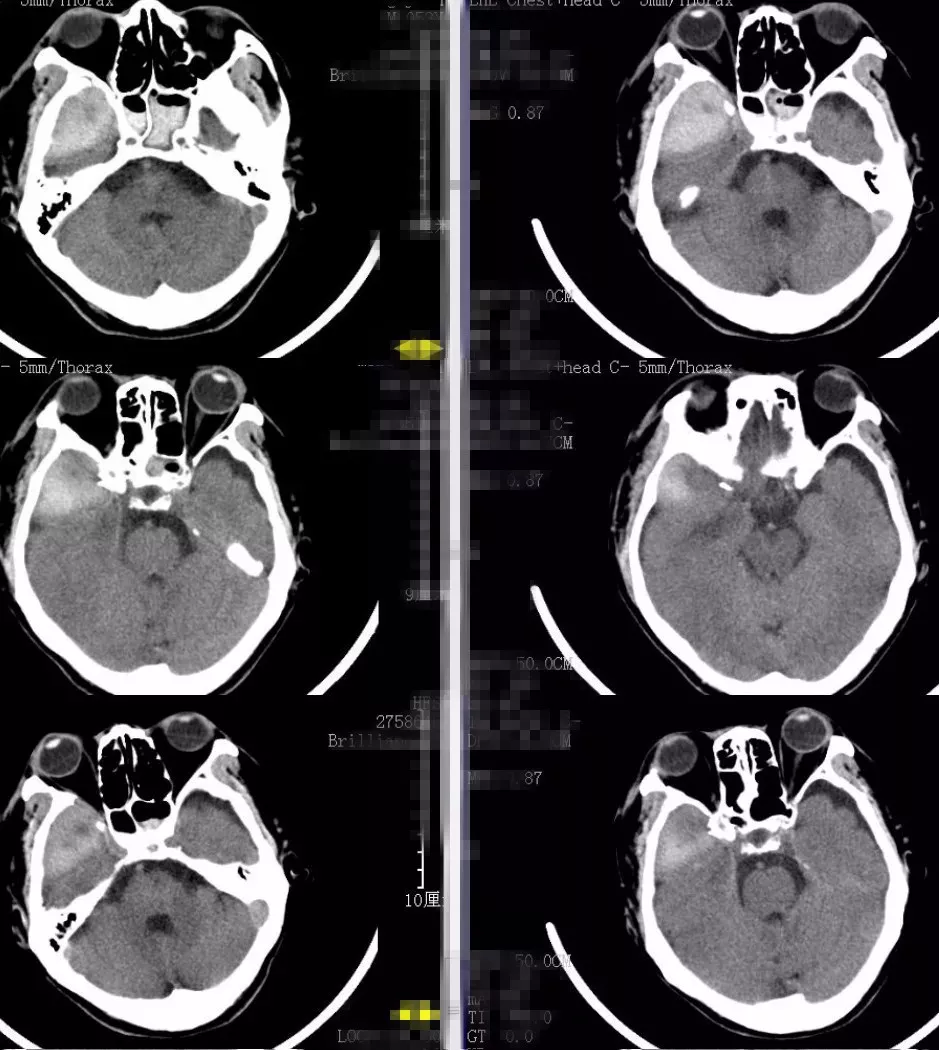

患者头痛头晕逐渐好转,右眼视力也较前好转。胸腔积血明显减少,拔除引流管。遂转骨科行右肱骨手术治疗。骨科手术后患者病情恢复可,也无明显头痛加重等。出院前常规给予复查头颅CT(2018-2-5)提示右颞部硬膜外血肿新鲜出血(图4)。考虑暂缓出院,并转回李惠利医院神经外科。患者转回神经外科后当天出现剧烈头痛,再行复查头颅CT及预约CTA。2018-2-9 CT提示右颞硬膜外血肿较前明显增多(图5)。

图4. 骨科术后复查头颅CT(2018-2-5)提示右颞部硬膜外血肿新鲜出血。

图5. 2018-2-9 CT提示右颞硬膜外血肿较前明显增多。